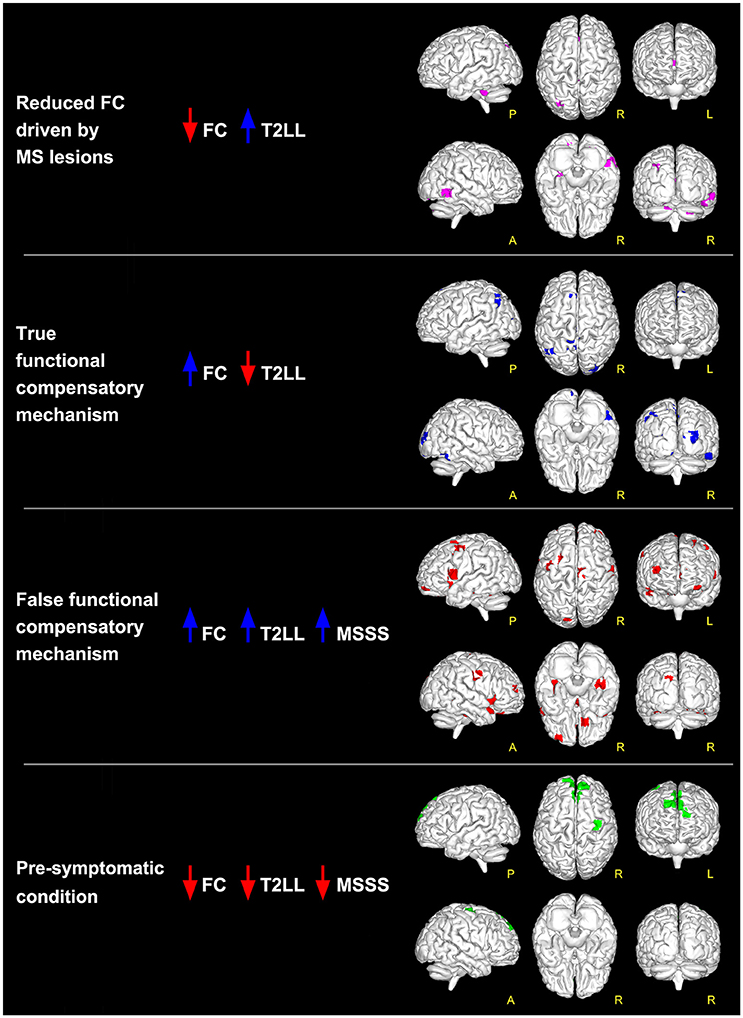

new.qq.comFrontiers | Functional Connectivity Alterations Reveal Complex

new.qq.comFrontiers | Functional Connectivity Alterations Reveal Complex

www.frontiersin.orgalterations frontiersin mechanisms mild reveal functional clinical remitting radiological connectivity sclerosis relapsing complex multiple status based figure fneur

www.frontiersin.orgalterations frontiersin mechanisms mild reveal functional clinical remitting radiological connectivity sclerosis relapsing complex multiple status based figure fneur

nguyeindo.comBetween-group Differences In Baseline Radiological (a -d), Neurological

nguyeindo.comBetween-group Differences In Baseline Radiological (a -d), Neurological